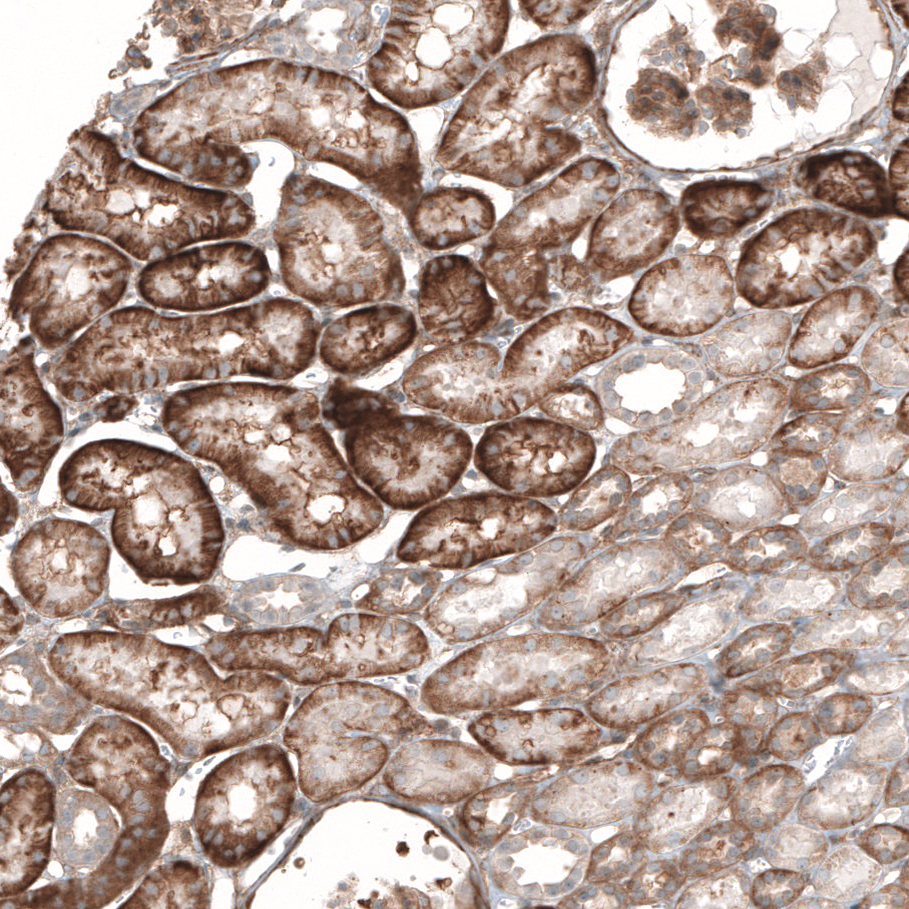

Immunohistochemical staining of human liver shows moderate to strong membranous positivity in hepatocytes.